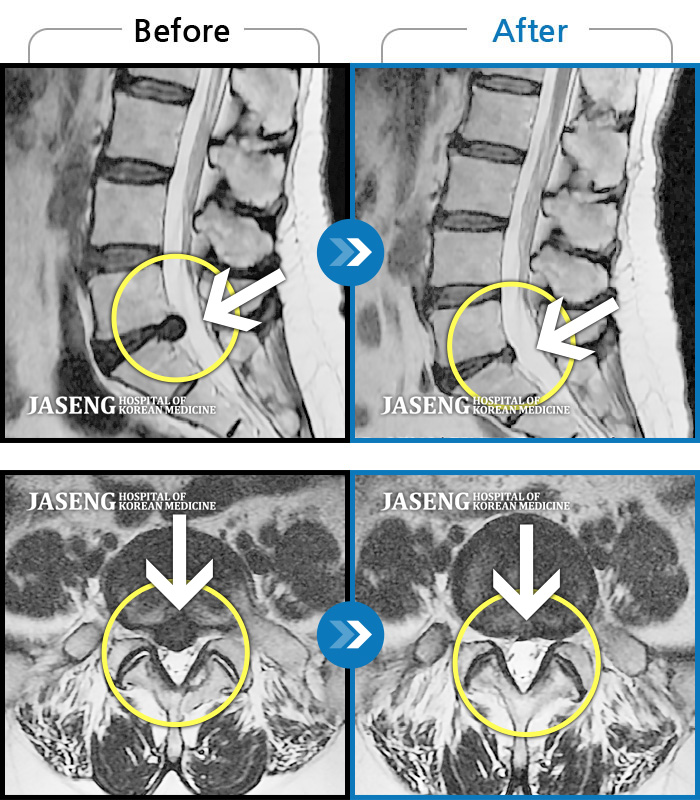

허리디스크

잠실 · 한상욱 원장

허리통증과 함께 좌측 엉치, 허벅지, 종아리 후면으로 저림이 심하여 걷기가 힘들어요.

촬영시기

2021.09.14 ~ 2022.05.14

2022.05.24